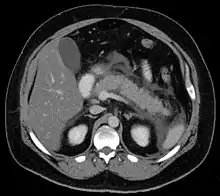

گاهی اسکن رادیوایزوتوپ، رادیوگرافی شکم، سی تی اسکن یا سونوگرافی لوزالمعده و آندوسکوپی مفید میباشد.